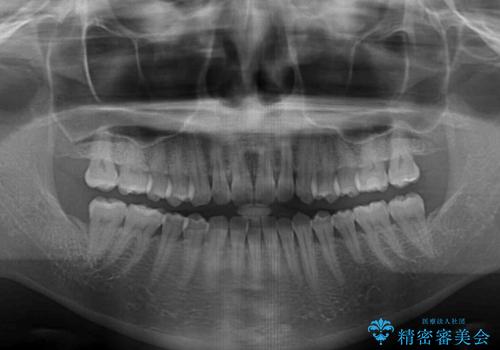

- 前歯のデコボコで前方に出ていることを気にして来院された患者様です。

上顎前歯が捻れて前方に飛び出しており、下顎前歯もそれに沿うようにデコボコとなっていました。

IPR(歯と歯の間を削る処置)によりスペースを獲得して上下顎前歯のデコボコを改善し、飛び出している前歯が引っ込むように設定し、インビザラインにて矯正治療を行うこととしました。